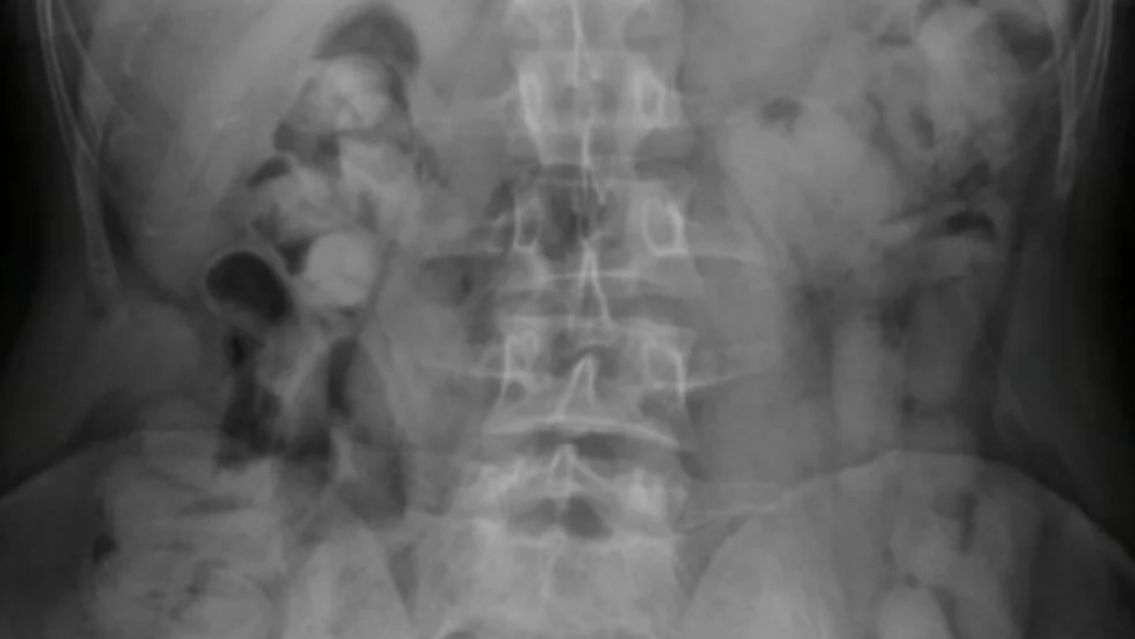

Ante la presunción de estar frente a un hecho ilícito, los uniformados tomaron contacto con el Juzgado Federal de Tucumán, el cual autorizó el traslado de los ciudadanos hacia el nosocomio local, a los fines de efectuar las placas radiográficas.

Los resultados de los estudios médicos confirmaron la presencia de cuerpos extraños en el interior de los estómagos de los pasajeros, quienes inmediatamente quedaron bajo observación.